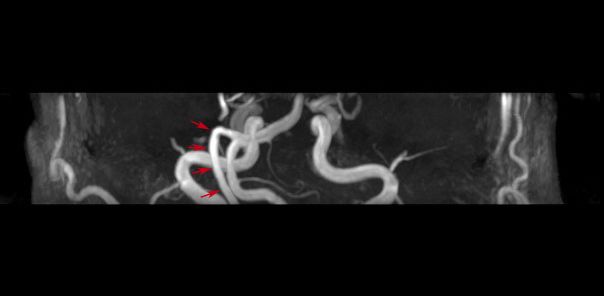

术前阅片考虑责任血管为右侧迂曲椎动脉,同时压迫面神经及三叉神经。

面肌痉挛及三叉神经痛均为右侧,常规右侧枕下乙状窦后开颅。

术后患者面肌痉挛及三叉神经痛症状均消失,术后8天拆线后出院,进一步随访中。